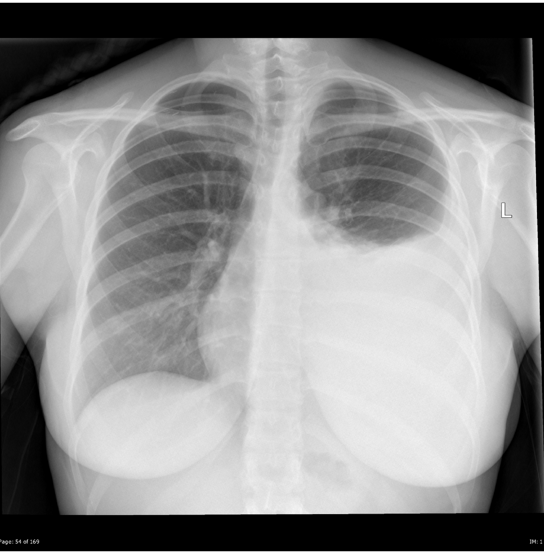

What is this showing? Collapse or consolidation?

Consolidation. Hilar are equal levels. Ill defined appearance